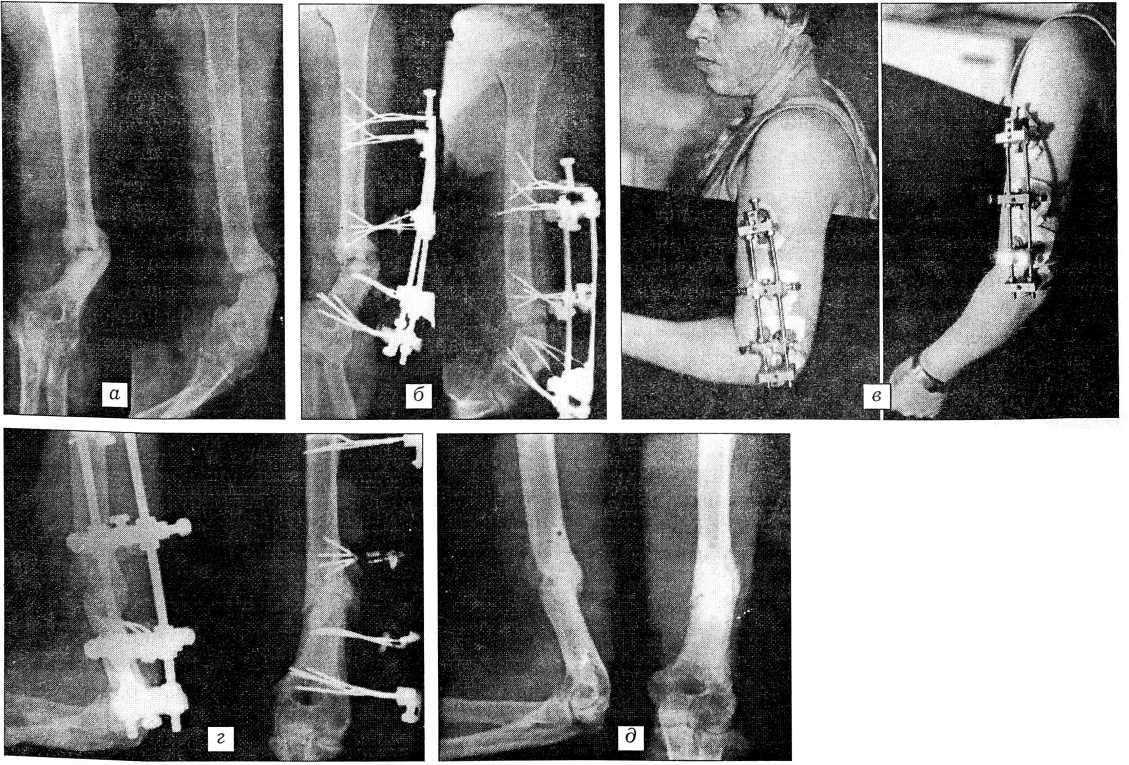

В качестве примера приводим следующее наблюдение.

Больной М.,33 лет, поступил в клинику с диагнозом: ложный сустав нижней трети левой плечевой кости, варусная деформация левого плеча, контрактуры левого плечевого и локтевого суставов (рис. 4, а). Отмечаются резкое ограничение объема активных и пассивных движений в левом локтевом суставе (сгибание 80°, разгибание 120°), ограничение отведения в плечевом суставе до 65°, варусная деформация в нижней трети плеча до 40°, гипотрофия мышц левой верхней конечности и надплечья.

Больному произведен внеочаговый остеосинтез левой плечевой кости анкерно-спицевым аппаратом (рис. 4, б, в). Начата дистракция. Репозиция осуществлялась спицами с упорными площадками, закрепленными в спицедержателях 3-й модели. В раннем послеоперационном периоде начато реабилитационное лечение, направленное на восстановление функции левого локтевого и плечевого суставов. Восстановление анатомической оси достигнуто через 15 дней после операции (рис. 4, г). Фиксация в аппарате продолжалась 23 нед. За это время достигнуты сращение плечевой кости (рис. 4, д) и практически полная амплитуда движений в смежных суставах.

Рис. 4. Больной М. с ложным суставом в нижней трети диафиза левой плечевой кости. а — рентгенограммы при поступлении; б — рентгенограммы после проведения внеочагового остеосинтеза анкерно-спицевым аппаратом; в — внешний вид левой верхней конечности в раннем реабилитационном периоде; г — рентгенограммы после устранения угловой деформации; д — рентгенограммы после демонтажа аппарата: сращение плечевой кости.